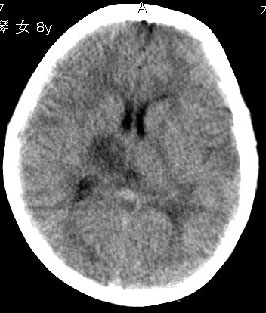

杨某,女,8y,家长述2006.10.13行破伤风疫苗注射后下肢疼痛,后自行粘贴膏药未见好转

,后续发现左上肢肢力下降。于2006.10.28在我院行ct检查,发现右侧基底节区片状低密度影,

无占位效应。ct值约:18~20hu。边界清晰,与相邻脑室无通连。未行增强扫描。余脑实质

未见异常。

急性播散性脑脊髓炎(acute disseminated ence-phalomyelitis, adem)也称免疫介导性脑脊髓炎,是一种少见的中枢神经系统脱髓鞘疾病,多数在发病前数天至数周有病毒感染或疫苗接种史,少部分无明确诱因。本病是自体免疫损伤所致的脱髓鞘疾患而不是病毒性脑炎。

支持adem的诊断。病史比较重要,其实左侧放射冠区白质亦见低密度,下面是我收到的一幅图片和英文资料。

adem is a neurologic disorder characterized by inflammation and damage to the myelin sheath of the brain and spinal cord, likely from a transient autoimmune response. it is a monophasic syndrome that is usually preceded by a viral illness, an upper respiratory infection, or vaccination. viruses that have most commonly been associated with adem are measles, paramyxovirus, varicella, rubella, and epstein-barr virus, although, with the advent of successful vaccination campaigns, the incidence of adem with these viruses (eg, measles) is dramatically reduced. as such, because of adem';s association viruses typically occurring in childhood, the disease occurs in children younger than 10 years approximately 80% of the time; only 3% of cases occur in adults.

急性播散性脑脊髓炎。